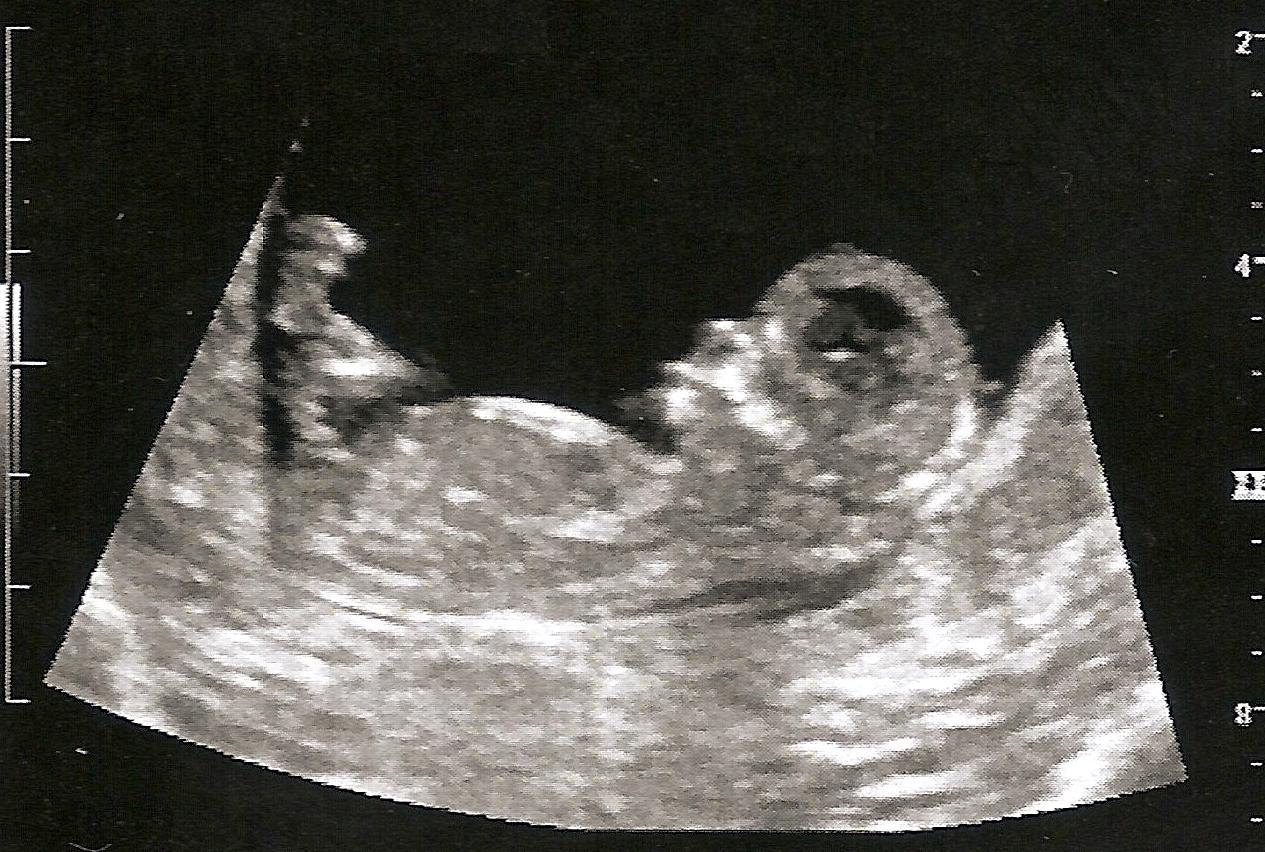

Please help girl or boy skull theory